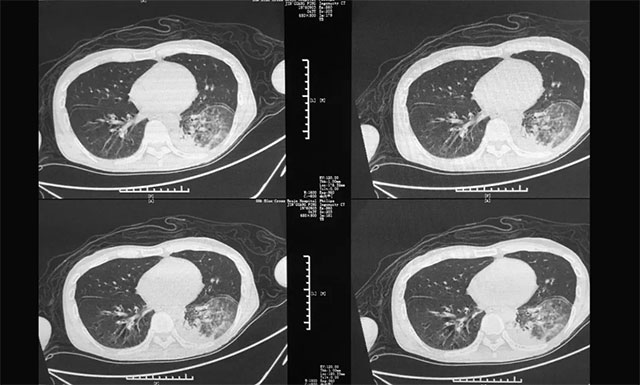

▲ 患者出现多种并发症:肺部感染严重

入院后,潘仁龙团队对陈先生进行了全面仔细的检查,根据其各项检查结果、目前出现的症状,并结合其20余年的饮酒和吸烟史以及外院诊治情况,陈先生最终被确诊为:1、使用酒精引起的戒断状态伴有谵妄;2、慢性酒精中毒;3、肺部感染;4、液气胸;5、大疱性肺气肿。